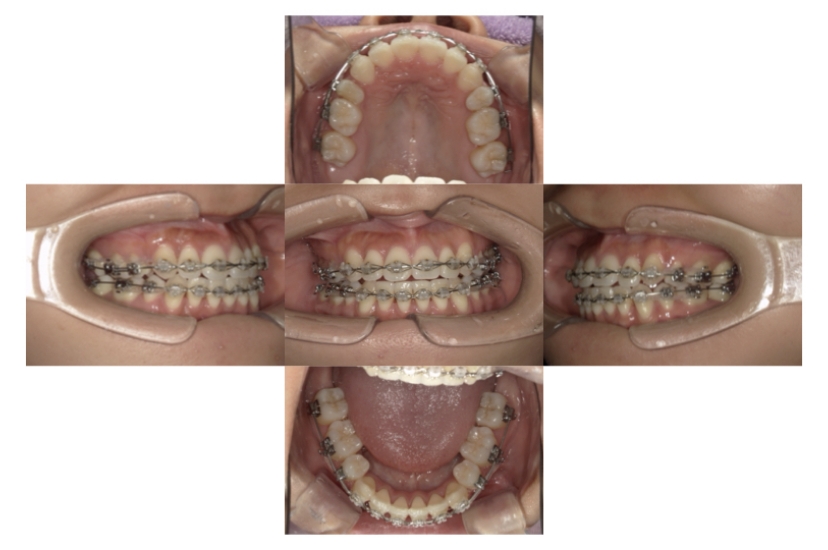

BEFORE

治療経過

AFTER

上下顎叢生(上下の前歯のガタガタ)のケースです。

装置はラビアル(上下表側)で、上下顎の小臼歯を4本抜歯を行っています。抜歯したスペースを使って、上下の前歯の後方移動と叢生(ガタガタ)の改善を行っています。

主訴 歯並びが悪く、舌を噛んでしまうのを治したい。

年齢・性別 27歳 男性

お住まいの地域 東京都大田区

治療方針 抜歯スペースを利用して上下前歯の叢生(ガタガタ)の改善

抜歯部位 上下顎左右第一小臼歯

使用装置 ラビアル(上下表側)、顎間ゴム

治療期間 3年1か月

治療回数 30回